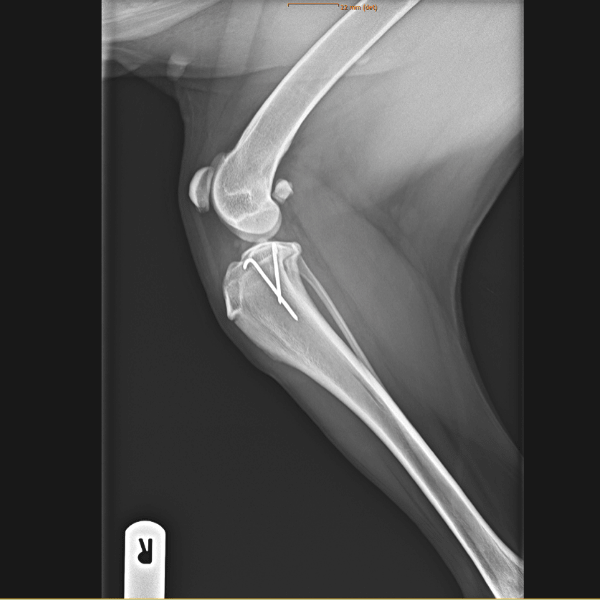

Ruptured medial collateral ligament in combination with a proximal Salter Harris fracture of the right stifle

Product: 1x Weldix® 2.3mm Suture Anchor

Elli the black flat-coated retriever mix was not even a year old when she was hit by a car. It was Elli’s right hindlimb that was injured in the car crash. She suffered both a salter harris fracture of the proximal tibia and a ruptured medial collateral ligament. Surgery was needed to allow Elli to walk again.

Dr. Riccarda Schuenemann performed the surgery, fixing the Salter Harris type I fracture with two 1.6mm pins both medial and lateral in the tibia. The medial collateral ligament was repaired by placing a Weldix® 2.3mm anchor proximally in the tibia then the ligament was attached with a locking-loop suture of a Prolene® 2/0 suture bridging the 5mm to the bone. The ligament residues were further supported by a Monoplus® 3/0 suture.